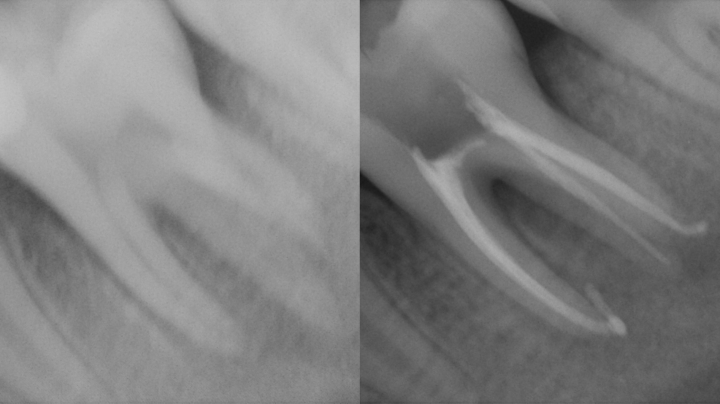

• 進行した虫歯:神経にまで達している場合は、根管治療(歯の根の治療)が必要になります

定期的なチェックやレントゲン検査で状態を確認する必要があります。この治療法(自費治療)には適応症がありますのでご希望の方は歯科医師にご相談ください。